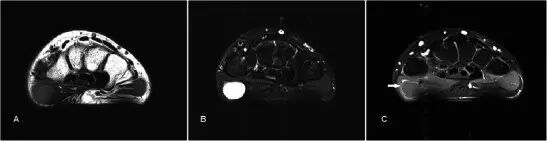

腱鞘的纤维肉瘤Fibrosarcoma of the tendon sheath 主要在35-55岁的成人年龄组,男性更常见。它们通常起源于膝关节和骨盆周围的关节囊或骨骼,更不常见的是软组织如肌肉或腱鞘[51]。 继发性形式发生在先前的照射或其它恶性转化与良性骨病症(如Paget氏病)的情况下。在MR上,损伤通常在反映纤维基质的T1w和T2w序列上具有低信号,但是可以在来自增加的细胞性或坏死的T2w序列上散布高信号区域(图20)。 增强后延时扫描有强烈的增强,并且增强的“辐条轮”状形态[52]。 在高级纤维肉瘤中常见的坏死和出血在低级中并不常见。 区分低度纤维肉瘤与纤维瘤及其变体可能是困难的。 确定诊断需要组织学分析。

图20.在47岁女性中肌腱鞘的纤维肉瘤,其表现为沿右手腕的尺骨方向的局部肿胀,在几个月内体积逐渐增加。 (a)超声显示沿着手腕的尺骨侧邻接伸肌桡侧的箭头所示的良好定义的hypoechoeic病变(箭头)。 (b)T1w序列显示邻接伸肌桡侧腕的低信号良好外切皮下病变(箭头)。 (c)病变主要是T2w序列上的低信号,小信号区域的高信号(箭头)指示更多的细胞/坏死组分。 (d)与仅显示最小增强的良性FTS(图3)相比,看到了非均匀增强